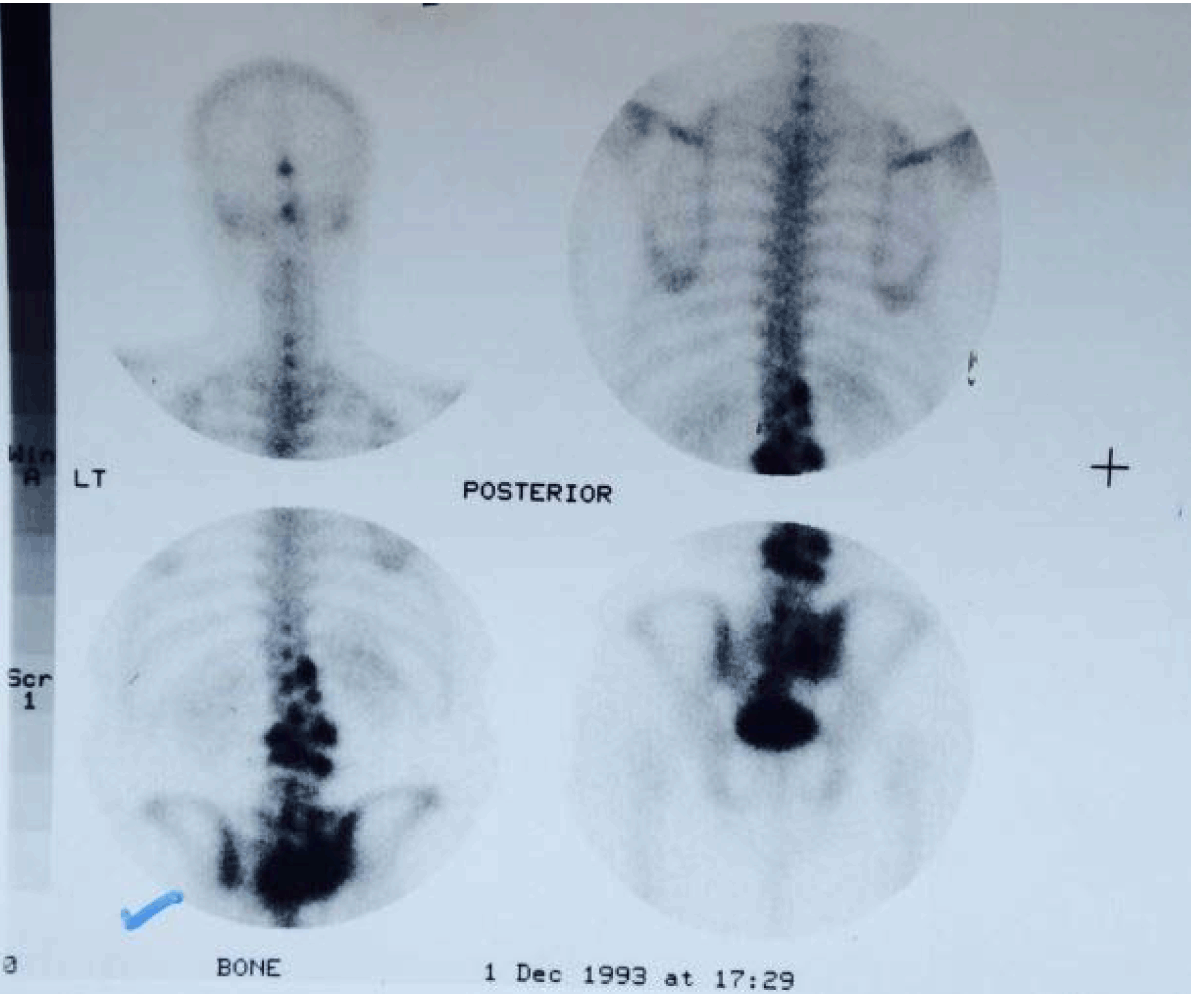

Considering the clinical status and young age of the patient, the radiological findings of multiple vertebral collapse without any history of trauma, effacement of the trabecular pattern with evidence of bony expansion and ground glass attenuation with no significant change in the radiographic findings during three years interval and with no evidence of compressive myelopathy in spite of the advanced spinal changes, a firm clinico-radiological diagnosis of a benign pathology was made with fibrous bysplasia as the possible diagnosis. A nuclear bone scan revealed high uptake of the tracer in the involved vertebrae (Figure 3). Computed tomography (CT) scan of the lumbosacral spine revealed expansile destructive lesions of multiple vertebrae (Figure 4) but these findings did not help in confirming or refuting the diagnosis of fibrous dysplasia.

Figure 3: Nuclear bone scan show increased uptake of the radiotracer by the involved vertebral bodies and the sacrum. Rest of the bones appear normal.